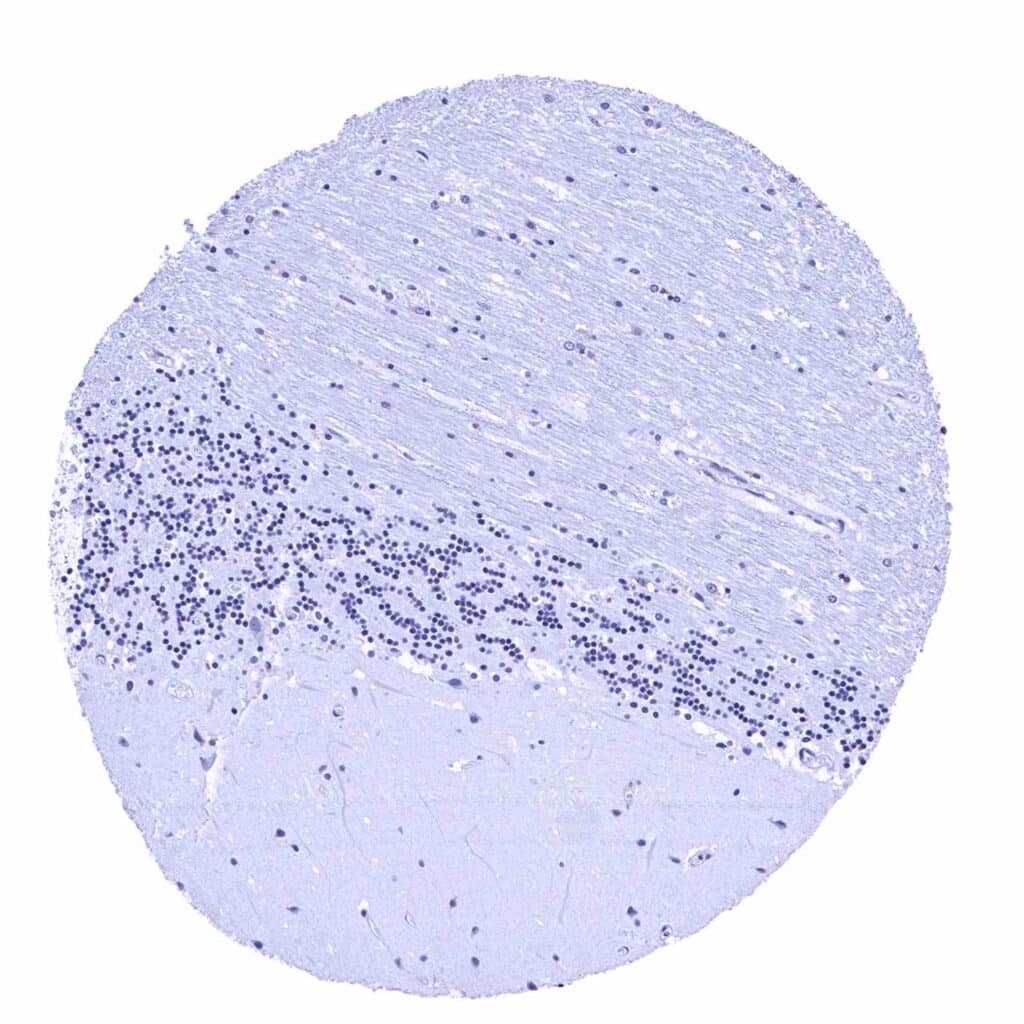

Cerebellum (molecular layer, Purkinje cell layer, granule cell layer, white matter)